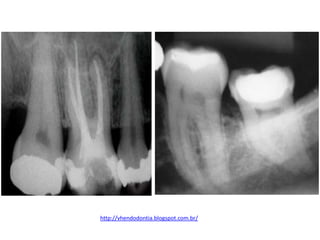

• Os dentes submetidos a tratamento endodôntido

precisam ter a câmara pulpar hermeticamente

vedada tanto entre as sessões quanto após o

término do procedimento. (PINHEIRO et al.,

1997; PECORA, 2002).

patrickbaltieri.blogspot.com.br/2011/08/procedimentos-pre-restauradores.html